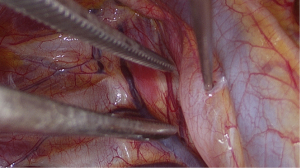

The SVI VATS procedure has been previously published (20). This section briefly summarises the procedure. First, a short-acting muscle relaxant (mivacurium) was introduced, to insert the double-lumen endotracheal tube. During the relaxation period, surgical incisions were made on the right side, as per routine practice, after local infiltration with 2% lidocaine. Subsequently, the following surgical incisions were made: a 3-cm utility incision in the mid-axillary line, a 1-cm submammal fold incision for the camera, and a 5-mm incision for the instrument between the submammal fold and sternum. To block the cough reflex, 5 mL of 0.5% bupivacaine was administered near the right vagus nerve (Figures 1-3), and 4–5 mL was administered between two and five intercostal nerves close to the spine (paravertebral blockade) (Figure 4). After elimination of the short-acting muscle relaxant (mivacurium), the patient breathed spontaneously without coughing, and in some cases, 4–6 positive end-expiratory pressure (PEEP) was administered to maintain perfect oxygenation. During MG, complete thymectomy was performed by removing the thymus and perithymic fatty tissues. As a routine procedure, the right pericardium-diaphragm angle fat, aortocaval groove, and aortopulmonary window fat were removed. Phrenic nerves were identified on both sides. The innominate vein was visualised, and all horns of the thymus were dissected immediately into the neck. Additionally, accessory horns, commonly under the innominate vein, were routinely examined and were not overlooked. The thymus was then dissected up to the left phrenic nerve, which was identified after opening the left pleura using a 30° viewing-angle optical camera. Anaesthesia provided pressure support ventilation (PSV) when the left side was opened, although inspiration and expiration were managed by the spontaneous ventilation of the patient alone (20). The specimen was placed in an Endobag and removed from the thoracic cavity through an axillary incision. At the end of the operation, a 28-Fr chest tube was inserted through a 10-mm port into the operated area.